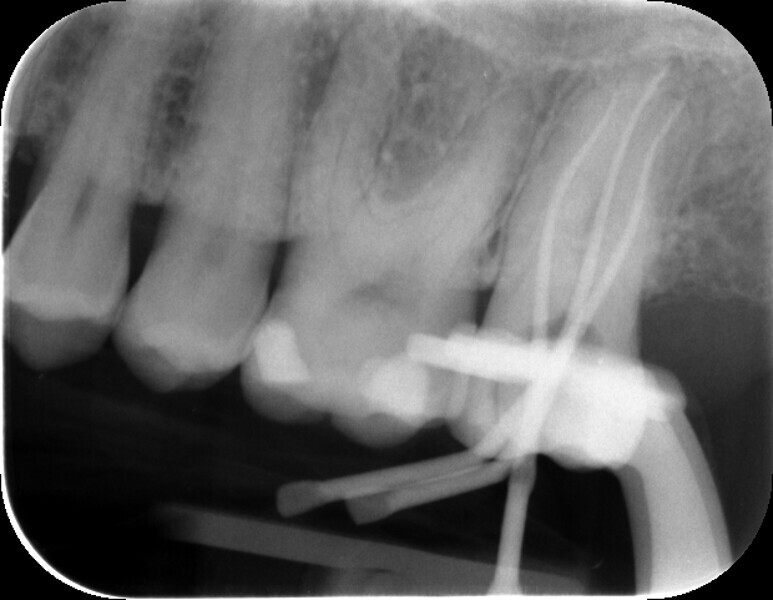

Fig. 2: Measurement radiograph for working length control.

After creating the access cavity, the individual root canals were probed and expanded under the operating microscope using a diamond-coated ultrasonic tip. The respective working lengths were determined with the aid of an apex locator. A measurement radiograph was taken as a confirmation and showed that the lengths matched the electronic measurements (Fig. 2).